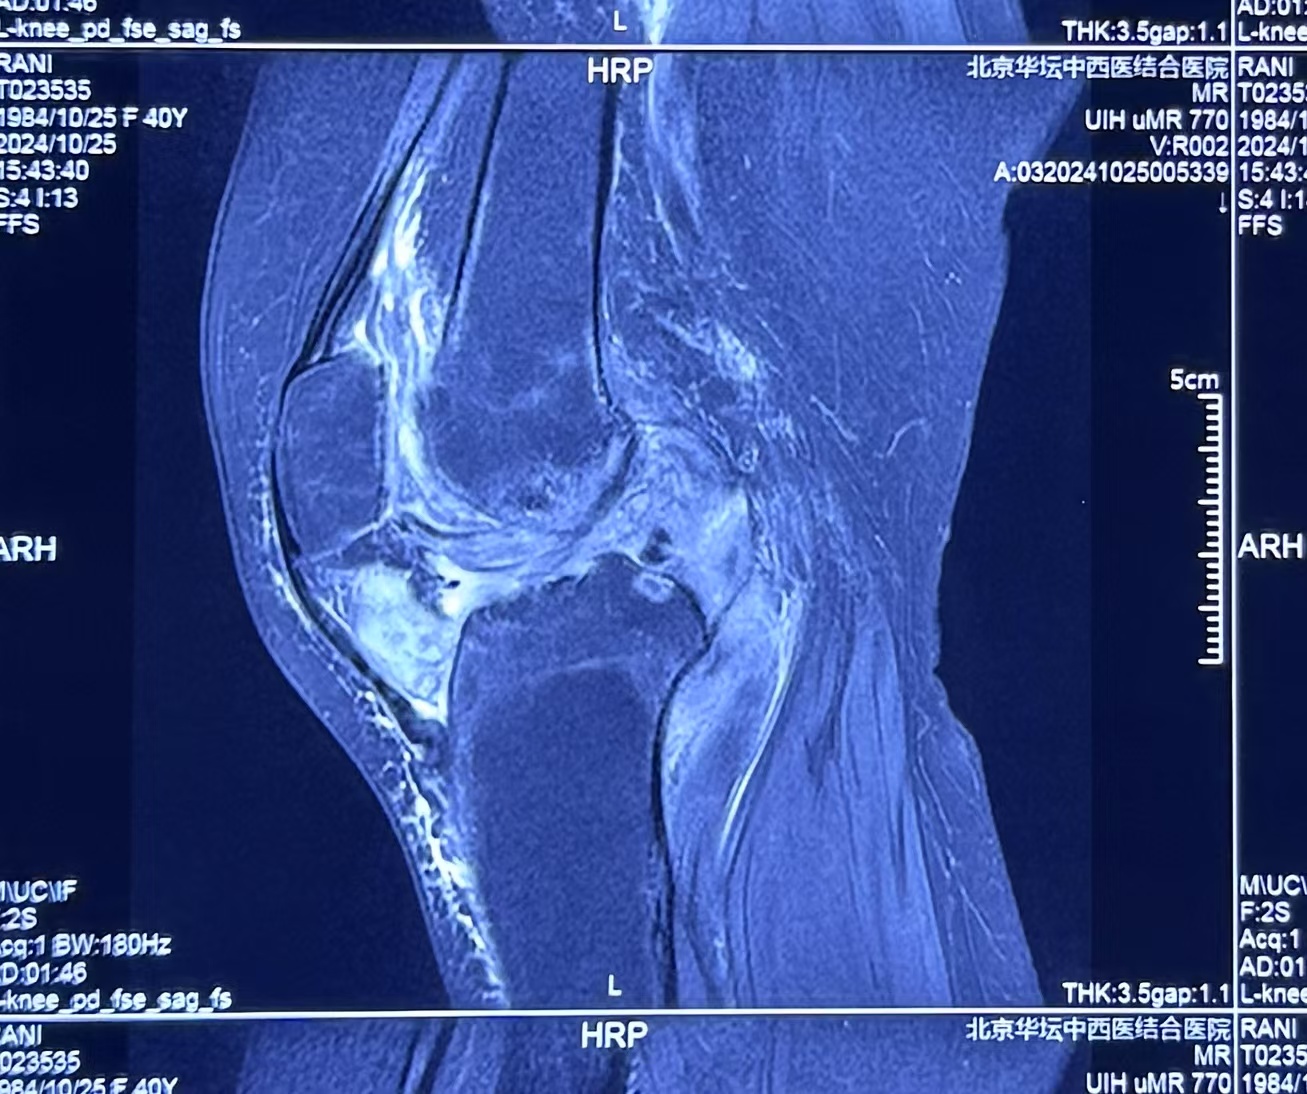

去年 11 月,患者慕名来我院就诊,骨科周昊嵬主任通过仔细阅读患者携带的外院核磁及 X 光影像片发现:关节腔内存在特征性低信号结节影,滑膜呈绒毛状增生,合并软骨下骨侵蚀及交叉韧带损伤。结合临床表现及影像特征,修正诊断为色素沉着绒毛结节性滑膜炎(结节型)。该疾病虽属良性病变,但具有类似恶性肿瘤局部侵袭性生长特性,好发于 20-40 岁人群,膝关节为常见受累部位。

经多学科讨论认为,患者左膝关节的病变已处于晚期,病变滑膜的增生侵袭已经导致左膝关节的软骨、韧带以及部分软骨下骨结构的严重破坏。常规病灶清理手术恐难以实现彻底清除病变、修复骨缺损,从而难以恢复病膝的生理功能。膝关节置换可能是唯一的选择,但传统膝关节置换术式对于年轻患者的远期功能维护存在局限。周昊嵬主任团队经充分医患沟通后,决定采用加长杆的特殊假体进行关节功能重建。